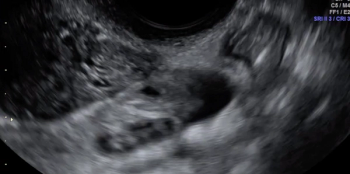

In this clip, fluid within the rectouterine pouch introduced following saline-infusion sonoPODography allows for appreciation of adhesions and a peritoneal pocket (enclosed fluid due to a defect in the peritoneum). These are two classic features of superficial endometriosis.

Although not clearly depicted in this clip, deep endometriosis likely is present posterior to the uterus at the level of the internal cervical os, as demonstrated by the irregular, hypoechoic area.